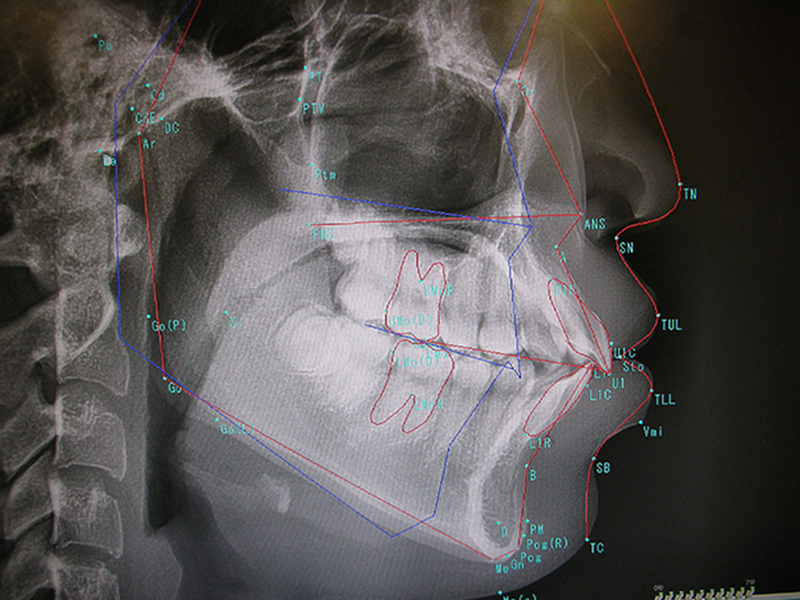

当院では矯正用の特殊な顔のレントゲン診査(セファログラム)を行います(下写真)。

矯正用ソフト解析を行い、理想的なの顔の形と患者さんの顔の形との比較を行います。患者様の顔のゆがみの状態をより正確に把握できます。

矯正の診査には、矯正の診査=セファログラム解析が必要です。何通りかの治療方針が立案されます。

歯を抜かないで矯正すべきなのか、歯を抜いて矯正したほうがよいのかを診断することができます。